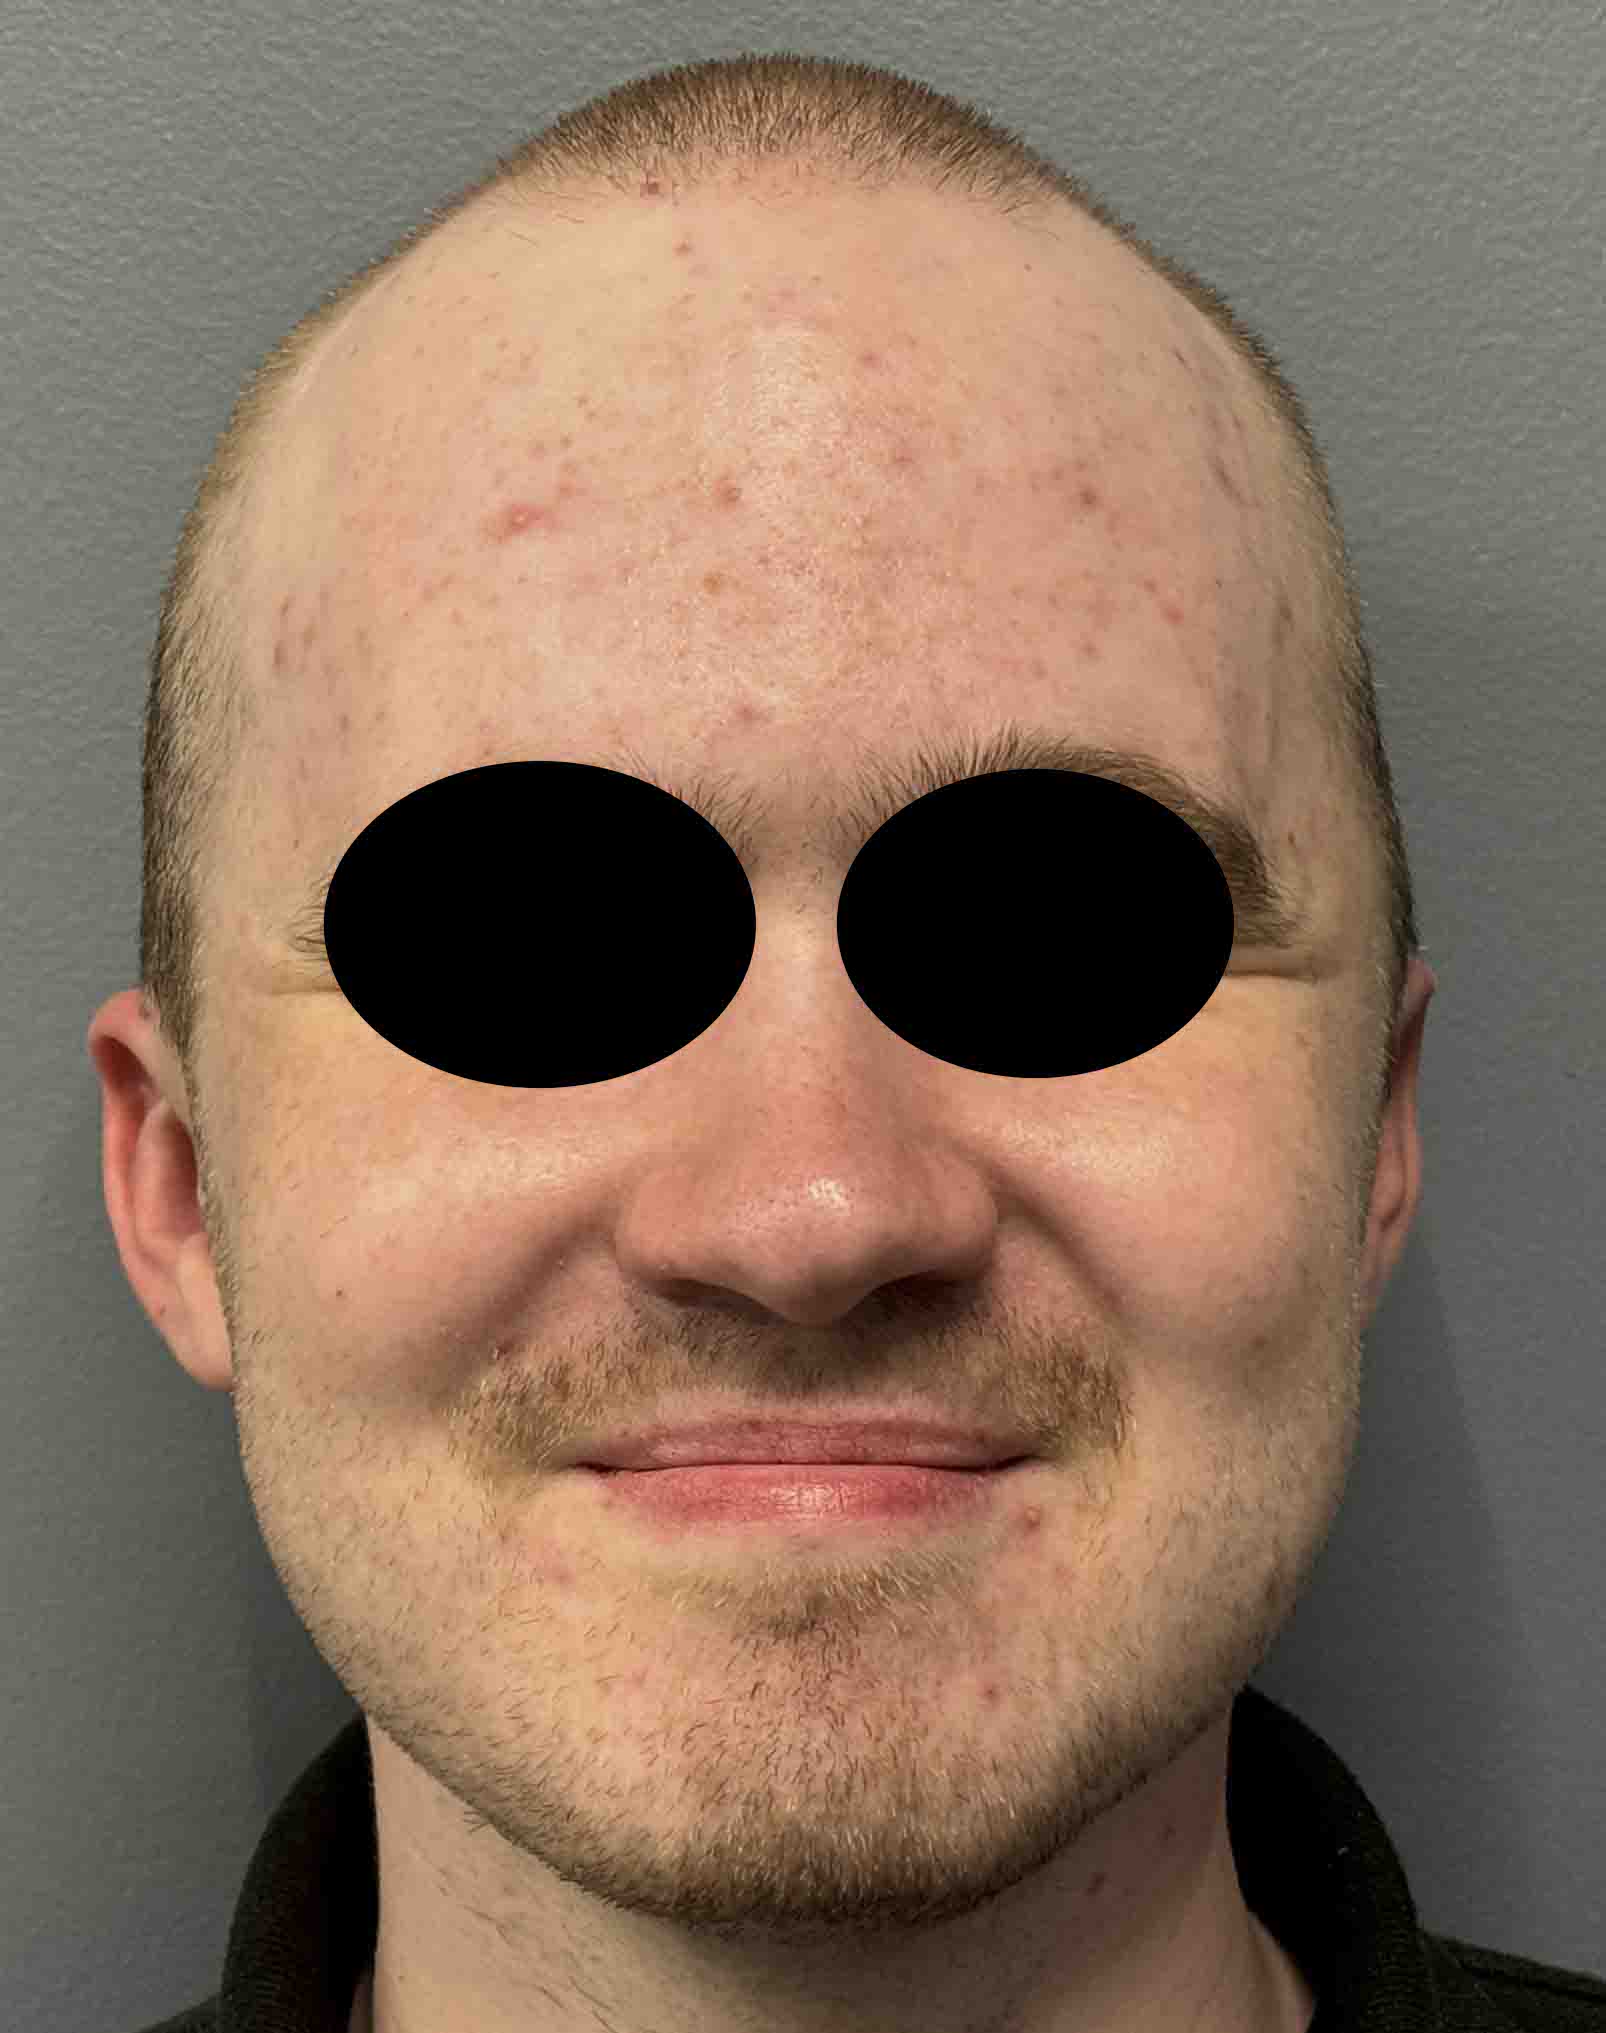

Patient 100

Desire for reshaping of an asymmetric flat back of the head in a shaved head male.

A combined back of the head reshaping procedure was done with a custom skull implant, sagittal ridge reduction and a right temporal muscle reduction.

Desire for reshaping of an asymmetric flat back of the head in a shaved head male.

A combined back of the head reshaping procedure was done with a custom skull implant, sagittal ridge reduction and a right temporal muscle reduction.